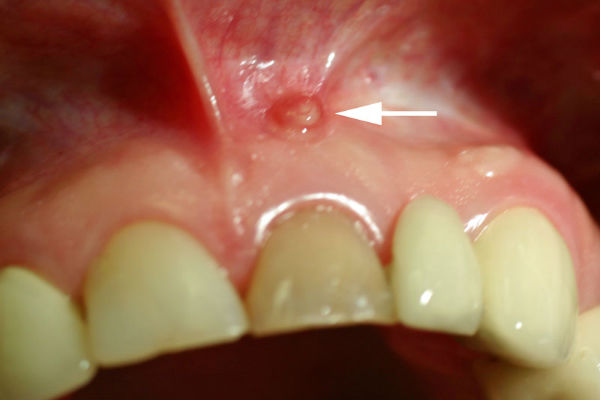

Fistula na zubnom mesu služi za pražnjenje gnoja iz mjesta nastanka u usnu šupljinu. Pojavljuje se u obliku male crvene izbočine na sluznici. Na nastanak fistula mogu uticati polomljeni zubi, upala desni, ali i fizički udarac u područje zubiju.

Fistula ne boli sama po sebi, bol ćete osjetiti na dodir ili pritisak. S obzirom na to da je ispunjena tekućinom, prepoznat ćete ju tek kada natekne.

Bakterije koje nastaju pri infekciji šire se prema vrhu korijena i prelaze u koštano tkivo. Stvara se gnoj kao reakcija organizma i time nastaje fistula na zubnom mesu, ali i ciste. Prisustvo fistule govori kako postoji infekcija u predjelu vrha korijena zuba koja se mora što prije tretirati.